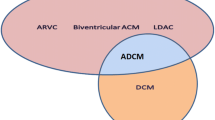

In patients with dilated cardiomyopathy (DCM), it is possible to find a broad range of bradyrhythmias and tachyarrhythmias. Bradyrhythmias and supraventricular arrhythmias can frequently occur in some familial forms such as lamin A/C mutations. Nonsustained ventricular arrhythmias (VA) are observed in about 40% of patients with DCM, but their prognostic role is not clear, and conflicting data have been published in the last 30 years. Multiple mechanisms can explain atrial and ventricular tachyarrhythmias in DCM. Reentry is associated with slow conduction across surviving muscle bundles within regions of interstitial fibrosis, but other mechanisms can be involved, as nonuniform anisotropy of impulse propagation, ion channel dysfunction, and reduced gap junction function.

Patients with dilated cardiomyopathy (DCM) can develop a broad range of bradyrhythmias and tachyarrhythmias including sinus node dysfunction, various degrees of atrioventricular block, interventricular conduction delay, and atrial and ventricular arrhythmias.

Conduction system disease (sinus node dysfunction, various degrees of atrioventricular block (AV), interventricular conduction delay, and bundle branch block) can occur with all cardiomyopathies, particularly in some familial forms such as lamin A/C mutations (LMNA), mitochondrial diseases, storage disorders (Fabry disease), and infiltrative diseases (amyloidosis).

Arrhythmias can initiate or aggravate acute heart failure (HF) in patients with preexisting heart disease. The arrhythmia-induced cardiomyopathy (AIC), known also as tachycardia-induced cardiomyopathy, is an important and potentially reversible cause of HF and DCM.

Two forms of AIC can be identified: in the first form, “arrhythmia-induced” cardiomyopathy, the arrhythmia is the only identifiable cause of ventricular dysfunction, and in the second form, “arrhythmia-mediated,” the arrhythmias aggravate ventricular dysfunction or worsens HF in subjects with underlying heart disease [35]. In patients with recent-onset HF and concomitant arrhythmias, a small LV end-diastolic diameter and mass index could indicate an AIC instead of a true DCM.